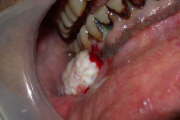

villikesest tekkinud haavand suu limaskestal